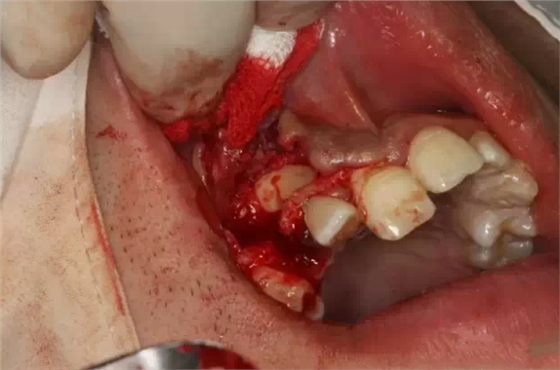

拔除滯留的右側上頜乳尖牙

行唇側梯形瓣切開、翻瓣

骨鑿去除唇側部分皮質骨

弧形鑿沿正畸牽引路徑去骨,作用是去皮質骨化,保證13能順利牽引到正常位置。

高速牙鉆修整路徑外形

繼續(xù)修整

暴露13唇面

清理牙冠唇側部分軟組織

止血、干燥